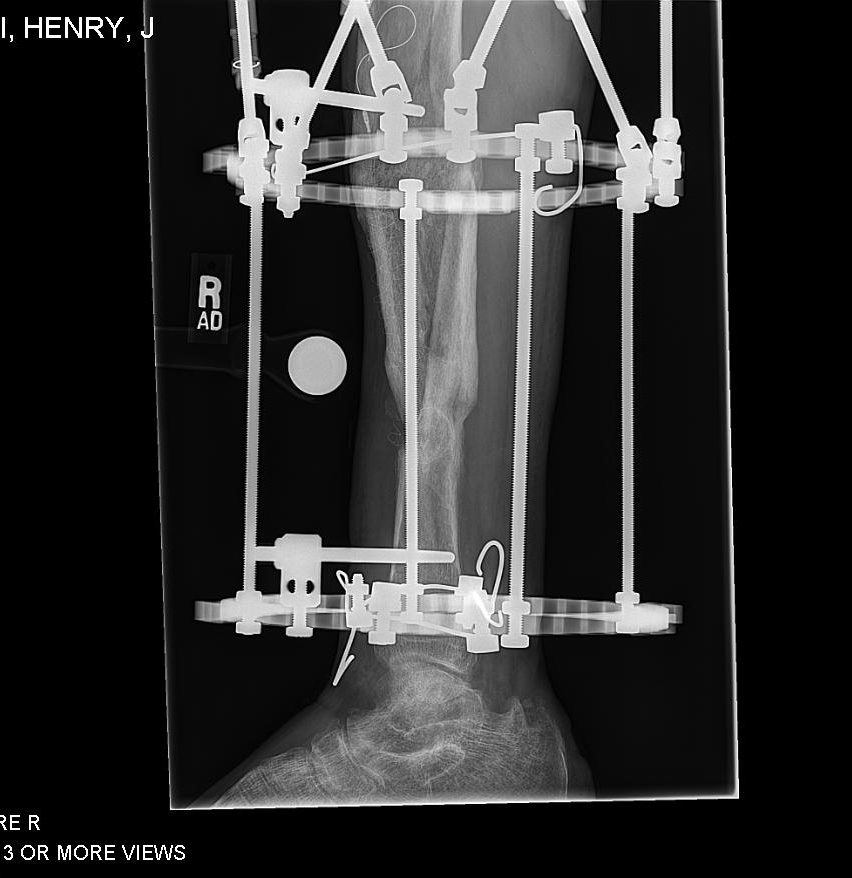

I was in a serious car accident in 2010 and broke both arms, both legs, pelvis, vertebrae and ribs. I was flown to a trauma 2 center in NJ. After being put back together from the initial accident, I healed for 3 months until I searched out Dr. Rozbruch at HSS. My right leg was short and angled due to the trauma. My left arm was a non-union and deformed. Sitting with Dr. Rozbruch for the first visit was amazing. He was confident in time that all of my issues could be repaired. It took multiple surgeries but a couple years later and he was right, HSS and Dr. Rozbruch fixed every single issue. I went from being told I may never walk again at the original hospital to now back to surfing, water skiing and playing basketball. Never in a million years did I think I would have such an incredible outcome. To add to the already stellar Dr. Rob Rozbruch and HSS, I became friends with Dr. Rob Rozbruch and together we created a new product and company over the past 5 years to aid patients in their healing. It is a device that aids patients in healing from lower limb injuries.